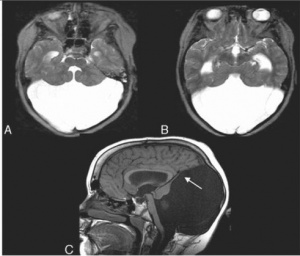

A mega-cisterna magna, is a controversial entity among experts. In general however, the term is applied to non-pathological prominance (usually exceeding 10 mm in antenatal imaging) of the retro-cerebellar CSF space and not associated with cerebellar abnormalities. There is a normal vermis and normal cerebellar hemispheres.

Typically seen as prominent retrocerebellar cerebrospinal fluid (CSF) appearing space with a normal vermis and normal cerebellar hemispheres.